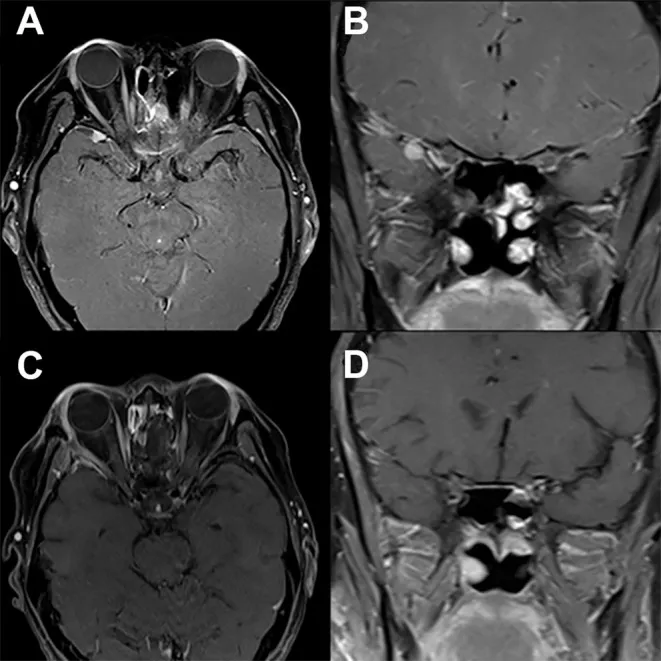

临床案例显示,一例既往接受嗅神经母细胞瘤切除术的患者,术前轴位(A)与冠状位(B)T1加权钆增强MRI影像显示沿右侧蝶骨大翼新发均匀强化病灶。经右侧改良外侧眶切开眶-颅入路实施病灶完整切除后,术后轴位(C)与冠状位(D)T1加权钆增强MRI证实病灶完全切除,患者神经功能完全恢复且未出现新增神经功能缺损。

该案例所采用手术入路系William T. Couldwell教授提出的创新性微创硬膜外经眶-颅外侧眶壁入路,专用于处理海绵窦区病变。此改良外侧眶切开术采用经典经眶切口,保留眦韧带完整性,通过打开眶外侧缘直达蝶骨大翼。该入路可显露出翼点开颅术的主要操作区域,包括侧裂池蝶骨段、视神经颈动脉池、前床突及海绵窦等重要结构。该术式既可用于获取前海绵窦区病变活检标本,也可用于切除小型病灶,同时适用于鞍旁区域动脉瘤及小型脑肿瘤的治疗。

为扩大显露范围,可磨除蝶骨大翼以暴露眶骨膜与颞叶硬脑膜,并可去除眶上裂上壁骨质。通过分离颞叶硬脑膜与海绵窦外侧壁,可显露出海绵窦及中颅窝结构。实施硬膜外前床突切除术后,可清晰显露颈内动脉床突段、近远侧硬脑膜环及海绵窦前壁。术毕需采用低剖面钛板复位固定眶外侧缘。术后随访证实,该入路可实现病灶完整切除且不引发新发神经功能缺损。